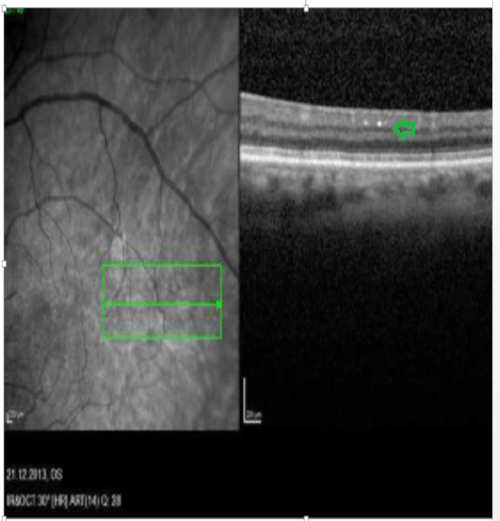

In 26 patients, our retina exams with FAF and OCT helped us see abnormal depositions mostly in the outer plexiform , ganglion and nerve fiber layers of the retina (Figures 1-4). The depositions were dot shaped and had different sizes.

Figure 2: OCT image. Small lesions in the outer plexiform and ganglion layers

These accumulations were mostly in the perimacular and perivascular areas. We believe that these plauqes are related to neurodegenerative disease. In the patients who used curcumin, it was possible to detect patchy hypofluorescent areas.